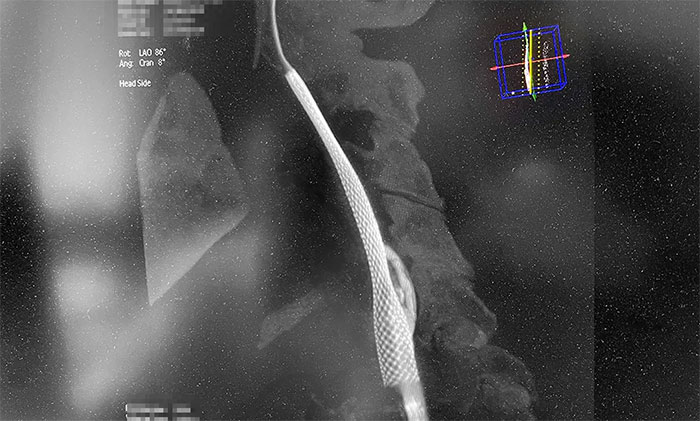

术中,超滑导丝、多功能导管经过反复尝试顺利通过左颈内动脉起始段,到达左颈内动脉远端显影段,路图见远端血管通畅,左大脑中动脉显影;随后,微导丝经多功能导管置于左颈内动脉海绵窦段,经微导丝送入保护伞至左颈内动脉岩骨垂直段并释放,再沿保护伞微导丝送入4x30mm球囊于左颈内动脉起始段,给予球囊扩张,撤除球囊后造影见左颈内动脉起始段再通,左颈内动脉、左大脑中动脉显影;最后,送入9x50mm支架,释放于左颈内动脉颈段至左颈总动脉末段,造影见左颈内动脉起始段显影明显改善,左颈内动脉、左大脑中动脉、左大脑前动脉显影可,行3D造影见左颈内动脉颈段显影改善。行支架CT见支架成形可,行XperCT未见颅内出血。

▲ 左侧颈内动脉闭塞顺利开通